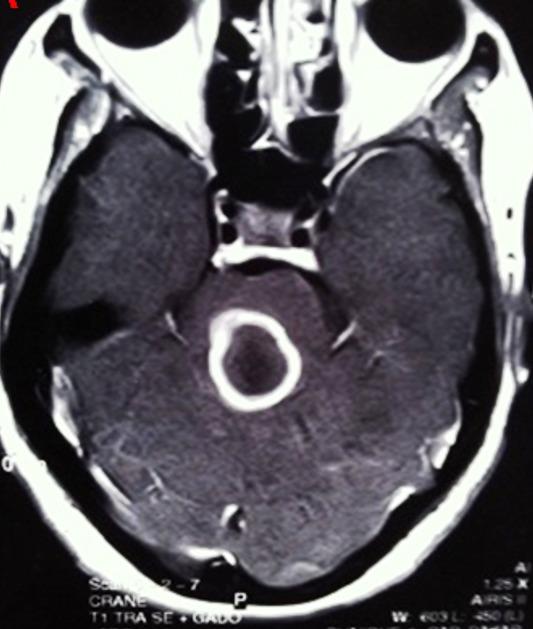

Tuberculosis is a major public health problem in developing countries. Cerebral tuberculomas is a tuberculous granulation tissue mass restrained and limited by immune defenses of the host. This study aims to describe the characteristics and the evolutionary profile of intracranial tuberculomas in Mauritania. Data of 34 patients with intracranial tuberculoma were collected retrospectively in several hospitals in the city of Nouakchott between January 2005 and June 2017. Evolutionary features of patients under treatment were analyzed. Our retrospective study involved 20 men and 14 women (sex ratio 1.4). The average age of our patients was 28.7 years. Twelve patients were less than or equal to 16 years. Symptomatology was dominated by increased intracranial pressure and seizures in 27 cases (79.41%) and 20 cases (58.82%) respectively. Intradermo tuberculin reaction was positive in 14 (41.17%) cases. Supratentorial lesion was found in 24 patients (70.58%). In all patients, therapeutic approach was based on multidrug chemotherapy for a period greater than or equal to 12 months. Surgical procedure was performed in 12 patients (35.29%). Outcome was favorable with complete healing without sequelae in 23 cases, reflecting a rate of 67.64%. Given the non-specific role of imaging exams in the diagnosis of intracranial tuberculoma and the lack of the stereotactic biopsy in our Country where the disease is endemic, we recommend to perform a two-month therapeutic test in patients with suspicious lesions.

结核病是发展中国家的一个主要公共卫生问题。脑结核瘤是一种受宿主免疫防御限制和局限的结核性肉芽组织肿块。本研究旨在描述毛里塔尼亚颅内结核瘤的特征和演变情况。2005年1月至2017年6月期间,在努瓦克肖特市的几家医院对34例颅内结核瘤患者的数据进行了回顾性收集。分析了接受治疗患者的演变特征。我们的回顾性研究纳入了20名男性和14名女性(性别比为1.4)。患者的平均年龄为28.7岁。12名患者年龄小于或等于16岁。症状以颅内压升高和癫痫发作为主,分别有27例(79.41%)和20例(58.82%)。结核菌素皮内反应阳性的有14例(41.17%)。幕上病变见于24例患者(70.58%)。所有患者的治疗方法均为多药化疗,疗程大于或等于12个月。12例患者(35.29%)接受了手术治疗。23例患者预后良好,完全愈合且无后遗症,愈合率为67.64%。鉴于影像学检查在颅内结核瘤诊断中的非特异性作用,以及在我们这个疾病流行的国家缺乏立体定向活检,我们建议对可疑病变患者进行为期两个月的治疗性试验。